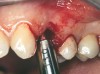

A 53-year-old female was referred for evaluation of a fracture of tooth No. 24. The tooth had been treated endodontically 5 years prior. The radiograph revealed a complete fracture of the tooth involving the crown (Figure 12). Tooth extraction and immediate placement of a an implant that was 10 mm in length and 3.75 in diameter was planned.

At the time of surgery, the tooth was extracted without harvesting any mucosal flap because the implant site was prepared by means of a pilot drill bur (Figure 13) and alternating osteotomes (Figure 14A and Figure 14B). The implant was positioned and showed primary stability. The implant was loaded 2 days after surgery. Then, splinted PFM crowns supported by custom gold abutments were delivered. At 6 months posttreatment, the radiograph revealed no bone resorption and the clinical result was optimal (Figure 15A and Figure 15B).

Figure 13 The drill bur was used to start the implant site preparation.

Figure 14A and Figure 14B Alternating osteotomes were used to prepare the implant site.